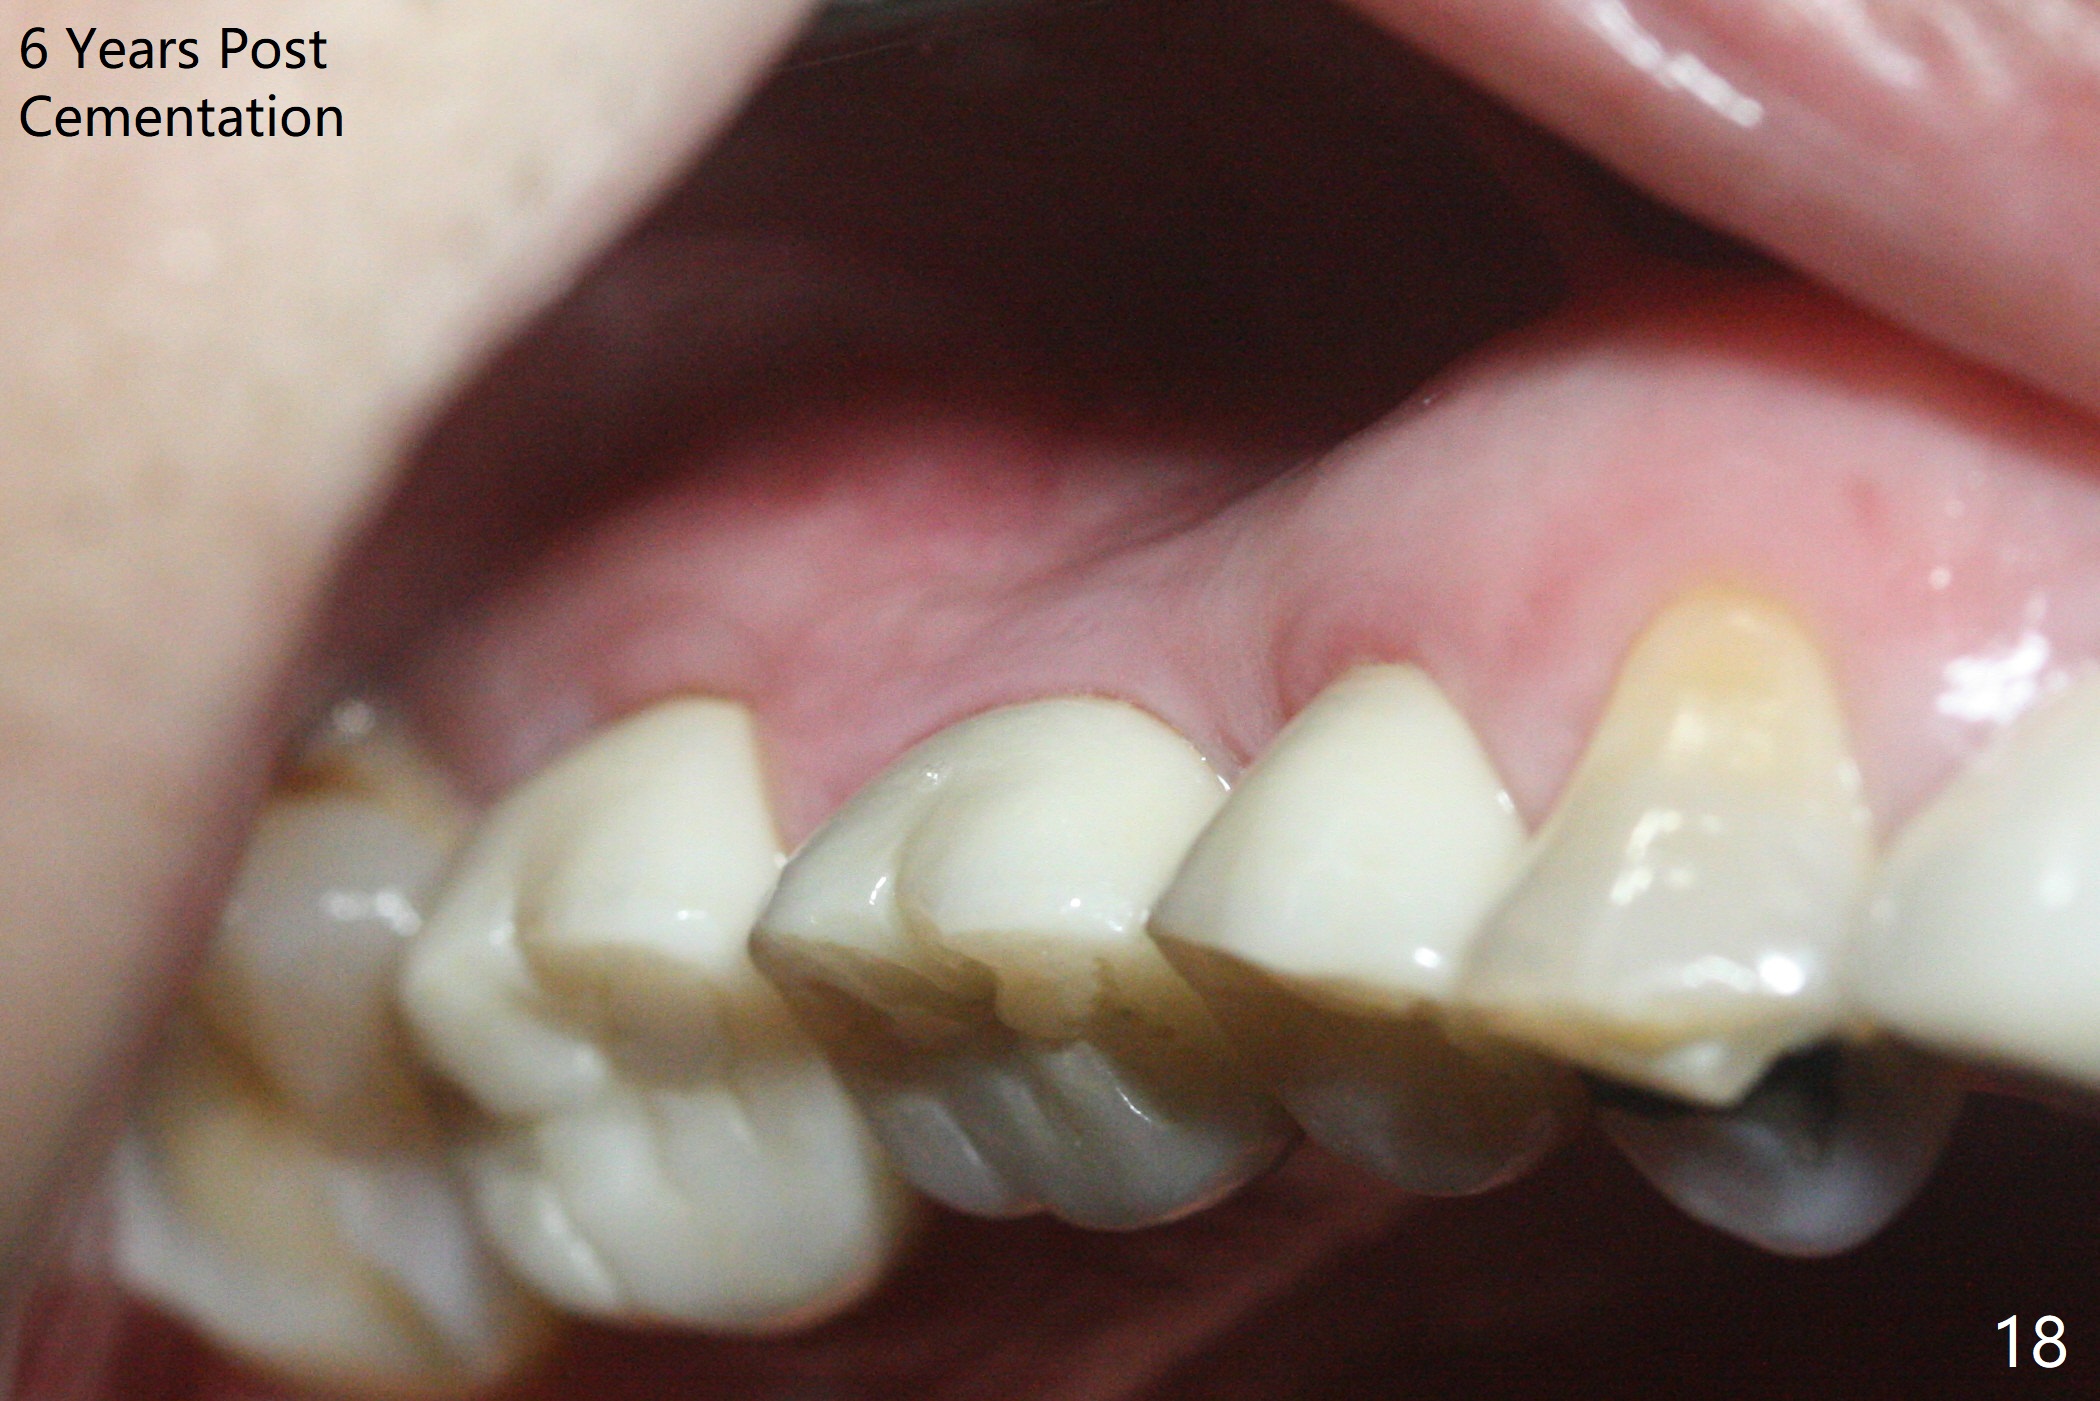

In brief, bone expanders or osteotomes can be used for bone expansion and condensation to improve primary stability of implant placement. No bone graft appears to be needed. The buccal concavity remains minimal 6 years post cementation (Fig.18). In fact he is a bruxer with torus palatinus (Fig.19). The bridge of #9-11 is loose because of subgingival fracture of the abutment of #11 for 2.5 years (Fig.20).